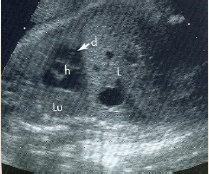

can you identify the fetal lt/rt sides?

also note the lung echotexture

what plane was this taken in?

how can you tell?

sp is spine in trans

what does the T sign mean?

why does it look that way?

it rules out 90% of pathology

both valves are closed

Left atrium lies closest to the fetal spine

Four chambers should be nearly equal in size

Right ventricular apex may appear thicker due to the presence of the moderator band

Foramen ovale flap into left atrium

Moderator band (AKA septomarginal trabecula in right ventricle). thick muscle.

Foramen Ovale (thin white arrow pointing down)